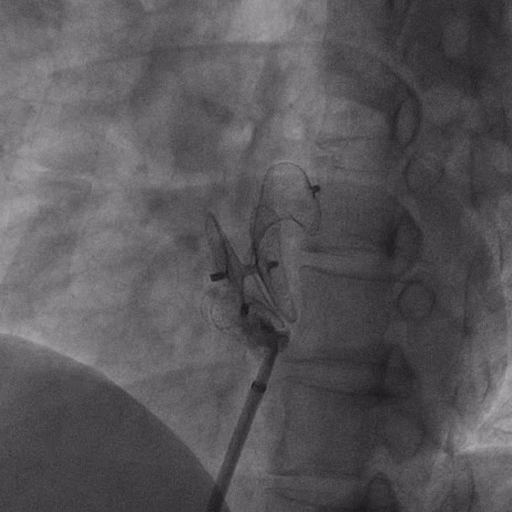

在獲得患者同意后,1月12日,尚福軍主任為患者進(jìn)行了PFO封堵術(shù)。術(shù)中造影可見封堵器殘余漏,尚福軍主任用精湛的技藝,順利通過封堵器殘余漏裂縫,將右心導(dǎo)管從右房送入左房,且順利到達(dá)肺靜脈;遂行卵圓孔未閉封堵術(shù)后殘余漏再次封堵;且完美釋放PFO封堵器,可見兩封堵器呈“馬蹄蓮”狀,再次術(shù)中造影未見殘余漏。

術(shù)后,小鞏生命體征平穩(wěn)。相關(guān)檢查顯示正常,且術(shù)后完善心臟彩超及發(fā)泡試驗(yàn),可見封堵器位置良好,未見右向左分流,發(fā)泡試驗(yàn)陰性。